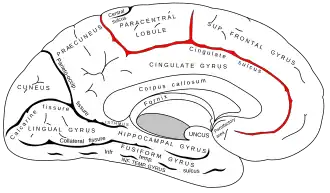

Medial surface of left cerebral hemisphere. (Paracentral lobule is shown in red.) | |

In neuroanatomy, the paracentral lobule is on the medial surface of the cerebral hemisphere and is the continuation of the precentral and postcentral gyri. The paracentral lobule controls motor and sensory innervations of the contralateral lower extremity. It is also responsible for control of blushing,[1] defecation and urination.

- The anterior portion of the paracentral lobule is part of the frontal lobe and contains a little portion of Brodmann's area 6 (SMA): this is because the paracentral sulcus (branch of the cingulate sulcus) does not correspond to the precentral sulcus on the medial plane.

- The posterior portion is considered part of the parietal lobe and deals with somatosensory of the distal limbs.

While the boundary between the lobes, the central sulcus, is easy to locate on the lateral surface of the cerebral hemispheres, this boundary is often discerned in a cytoarchetectonic manner in cases where the central sulcus is not visible on the medial surface.